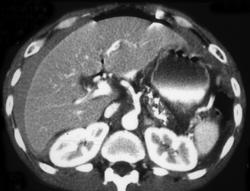

Menetrier's Disease